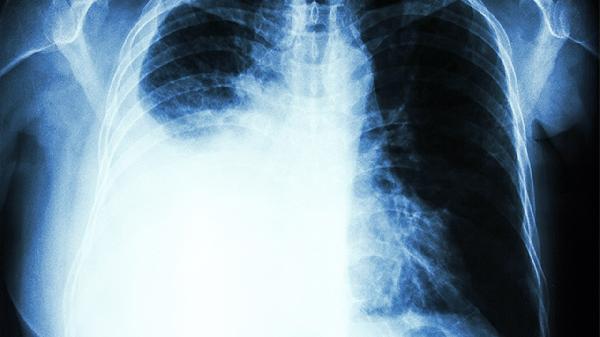

肺炎早期表现为刺激性干咳,随着病情发展可出现咳黄痰、发热等症状。肺力咳合剂作为辅助治疗药物,可通过抗炎作用减轻气道炎症反应。但重症肺炎患者需及时住院治疗,该药不适用于高热、呼吸急促等严重情况。